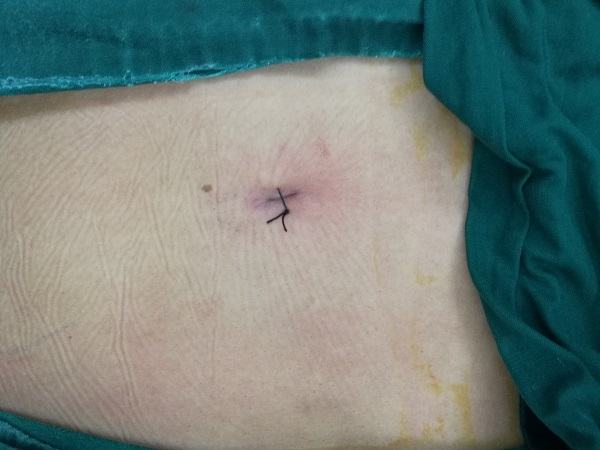

??????? 對(duì)于腰椎間盤突出癥,傳統(tǒng)的開放性切除手術(shù),創(chuàng)傷大、恢復(fù)慢,不利于患者的預(yù)后。椎間孔鏡技術(shù),則在手術(shù)室局麻下行微創(chuàng)切除腰椎間盤突出,術(shù)前不需過(guò)多的準(zhǔn)備及要求,術(shù)中手術(shù)切口只有1cm左右,術(shù)后即可解除神經(jīng)的壓迫,患者疼痛隨即消失下地行走,不用留置任何管道,立刻恢復(fù)正常生活。只需一個(gè)小孔,一個(gè)透視點(diǎn),即可完成腰椎椎間盤突出部分的切除,大大減輕患者的痛苦,縮短住院時(shí)間,真正達(dá)到微創(chuàng)手術(shù)外科的理念。

手術(shù)切口僅1cm